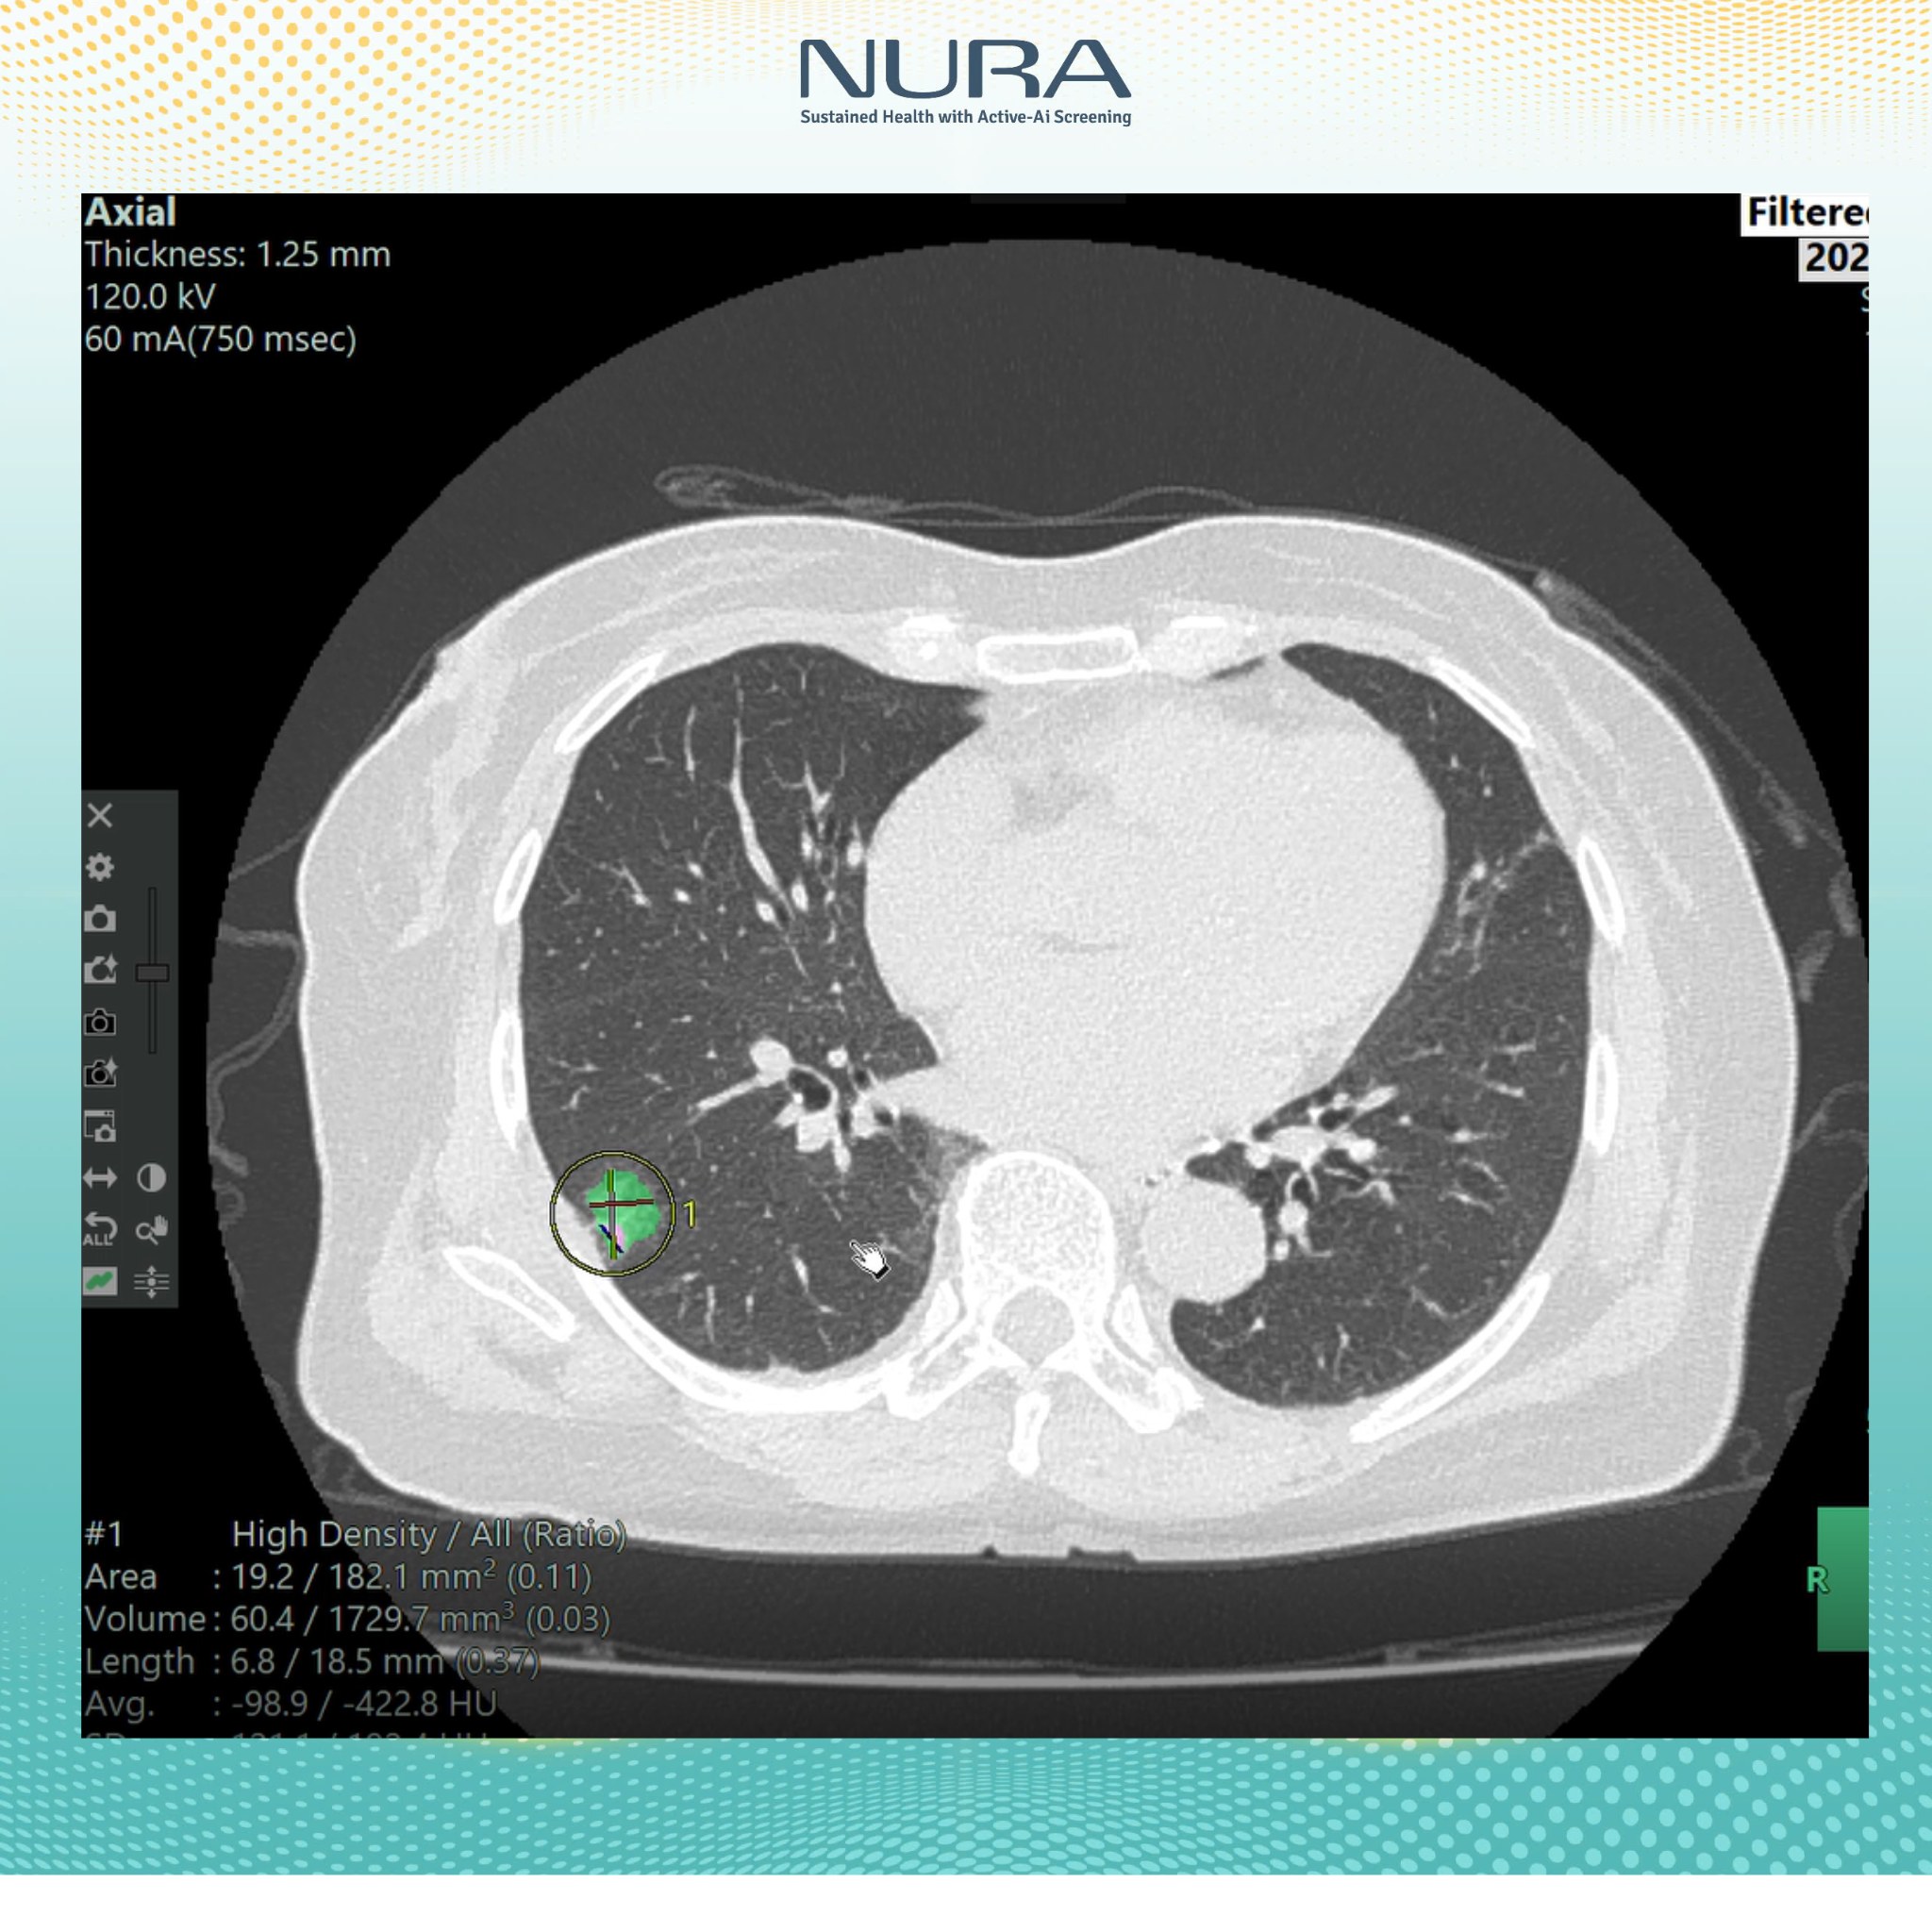

Trong số các thiết bị nổi bật tại trung tâm, máy chụp CT tại đây đã được các bác sĩ Nhật Bản công nhận là “chìa khóa vàng” trong tầm soát phát hiện ung thư. Được vận hành bởi đội ngũ bác sĩ giàu kinh nghiệm và tích hợp AI, hệ thống máy chụp này không chỉ giúp phát hiện các tổn thương rất nhỏ mà còn đảm bảo an toàn tối đa cho người được thăm khám.

“Công nghệ AI của NURA không chỉ đơn thuần là công cụ hỗ trợ, mà còn đóng vai trò quan trọng trong quy trình phân tích và nhận diện hình ảnh. Bằng cách thu thập và xử lý dữ liệu hình ảnh y khoa từ hơn 400 triệu ca bệnh được Fujifilm Nhật Bản lưu trữ trong suốt 10 năm, AI có thể nhận diện sớm các tổn thương bất thường – từ những nốt nhỏ nhất, kích thước từ 1mm trở lên.

Tại NURA, công nghệ AI được tích hợp trong hệ thống tầm soát công nghệ cao, cho phép lưu trữ và phân tích dữ liệu hình ảnh rõ nét, vượt trội so với phương pháp chụp cắt lớp truyền thống”, Đại diện NURA chia sẻ với báo chí.

Chỉ sau vài phút, kết quả sẽ được gửi về dưới dạng các hình ảnh cắt lớp chi tiết. Những lát cắt này cho phép bác sĩ phát hiện các tổn thương có kích thước từ 1mm, giúp việc chẩn đoán trở nên chính xác và nhanh chóng hơn rất nhiều.

- Về tính chính xác: AI không chỉ giúp phát hiện tổn thương từ rất sớm, mà còn tự động đo kích thước từng nốt nghi ngờ, đếm số lượng, đánh giá mức độ nguy cơ và hỗ trợ bác sĩ trong việc đưa ra quyết định chuyên sâu.